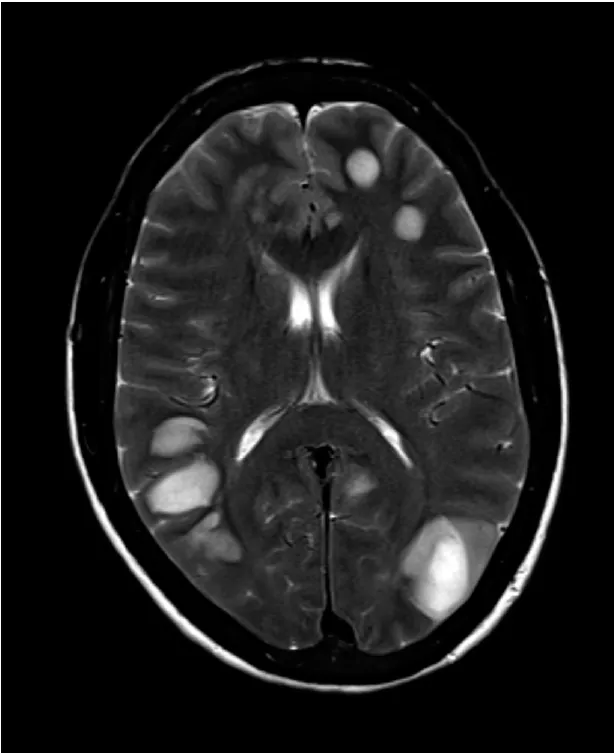

Confere esse caso clínico sobre rebaixamento do sensório e alucinação em paciente dialítico.

Sessão de desafio diagnóstico do NEJM que nos adiciona muito conhecimento sobre o tema vasculite!

A glomerulonefrite por C3 (GNC3) resulta de ativação descontrolada da via alternativa do complemento e pode simular uma GN pós-infecciosa. O diagnóstico correto depende do reconhecimento do padrão de deposição de C3 e da investigação genética. Com terapias-alvo como o eculizumabe e o iptacopan, identificar precocemente a GNC3 pode mudar o desfecho do paciente.